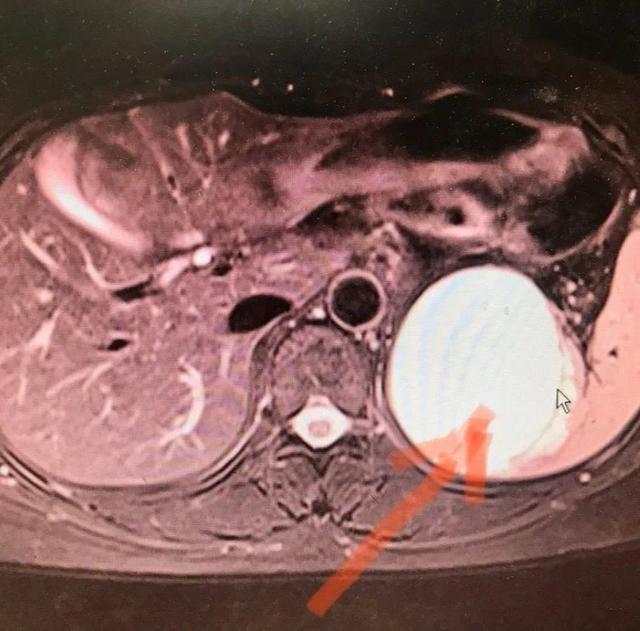

杨女士 , 46 岁 , 未孕 , 来长沙准备通过 " 试管婴儿 " 技术孕育宝宝 。 体检时 B 超发现脾脏有 7x6cm 大小肿块 , 于是来到长沙市第一医院肝胆外科就诊 。

肝胆外科熊立新主任医师查看患者后 , 认为杨女士准备怀孕 , 必须先解决脾脏肿瘤的问题 , 脾脏肿瘤巨大 , 有破裂出血的风险 , 建议行手术治疗 。 在熊立新的带领下 , 肝胆外科团队为杨女士实施了微创手术 , 在腹腔镜下将脾肿瘤完整切除 。 术后第二天 , 杨女士即下床活动及进食 , 恢复良好 。 目前杨女士已在积极备孕 , 准备迎接新生命中 。